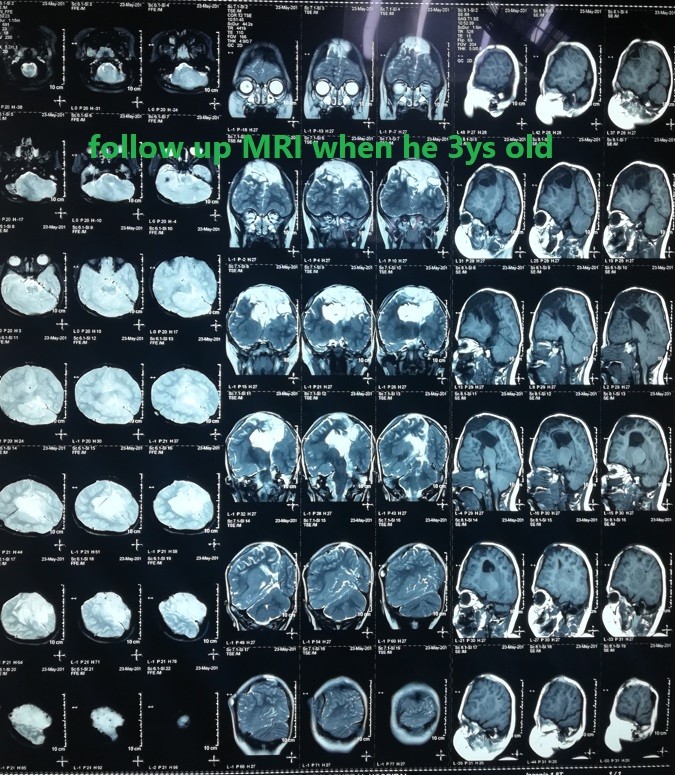

صور لحالة كاملة تم متابعتها منذ الأسبوع الأول من الولادة وحتي عمر ثلاث سنوات لطفل يعاني من قيلة مخية سحائية كبيرة .